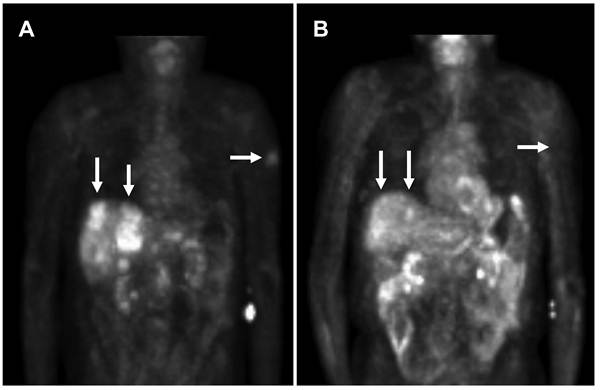

In view of the results from the patient's biopsy demonstrating elevated topoisomerase II mRNA (Table 2) and growth inhibition by doxorubicin (topoisomerase II inhibitor) in the patient's cell line (Figure 1), he was subsequently started on liposomal doxorubicin (40 mg/m2 every three weeks) through most of 2006 with excellent partial response (Figure 2). An index lesion in the liver was chosen and SUV on 10/18/05 averaged 6.4. One year later after the liposomal doxorubicin treatment, the SUV average decreased substantially to 2.1.

Figure 2

PET scan demonstrates tumor improvement while on liposomal doxorubicin treatment. A. Patient's PET scan prior to liposomal doxorubicin, and B. Patient's PET scan after 16 cycles (1 cycle = 3 weeks) of liposomal doxorubicin demonstrated shrinkage of tumor with treatment. Note the significant improvement in liver lesions as well as a left upper extremity skin lesion. Arrows indicate tumor lesions with notable reduction with treatment. In the central liver in the region of the caudate lobe there is a lesion which was present on 10/18/05 but no longer seen on 10/23/06 [Standardized Uptake Values (SUV) 10/18/05: Average 6.4, Max 8.3. 10/23/06: Average 2.1, Max 2.6]. In the periphery of the anterior segment of the right lobe there is a lesion which was large on 10/18/05 and much smaller on 10/23/06 [SUV 10/18/05: Average 3.2, Max 4.4. 10/23/06: Average 3.0, Max 3.5].